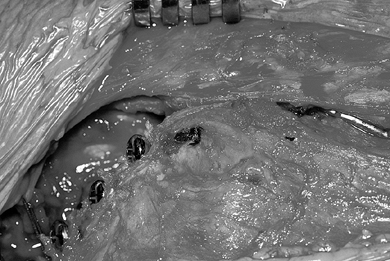

Arthrotomy of the hip joint may now be

performed with optimum timing since recovery of clear fluid suggests

that the hip joint has not been penetrated. Inspect the labrum of the

hip and resect any tears or detachments (Fig. 104.15).

The capsule may be left open to allow assessment of possible

impingement of the femoral neck caused by anterior reorientation of the

acetabulum.

Figure 104.15. Now re-reduce the acetabulum and perform an anterior arthrotomy to inspect the labrum, which was normal in this hip. -